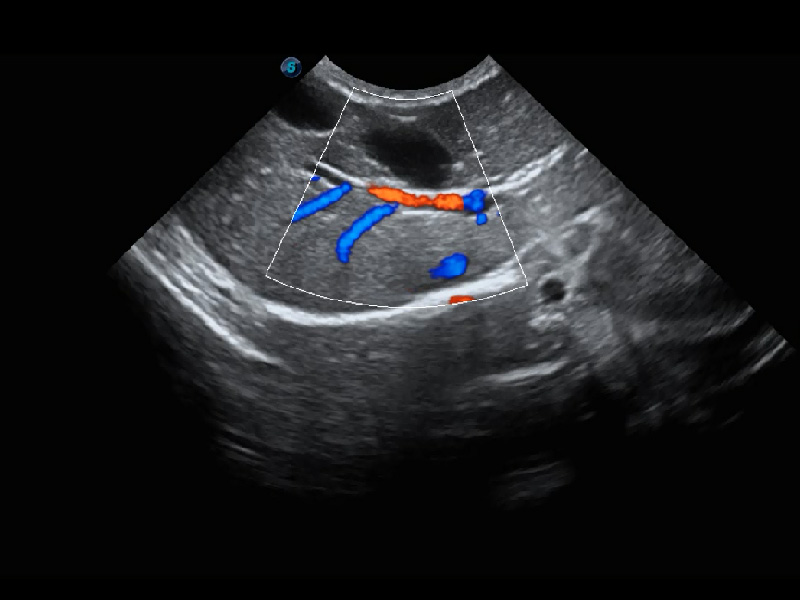

ProPet 60 作為一款高端臺(tái)式動(dòng)物超聲設(shè)備,為動(dòng)物醫(yī)生的日常診斷提供了一系列貼合動(dòng)物臨床需求、解決臨床實(shí)際問題的高級(jí)成像功能。憑借全系列高清探頭,滿足醫(yī)生對(duì)腹部、心臟、生殖、淺表、肌骨等成像的所有需求,切實(shí)幫助您提升檢查效率,提高診斷信心。